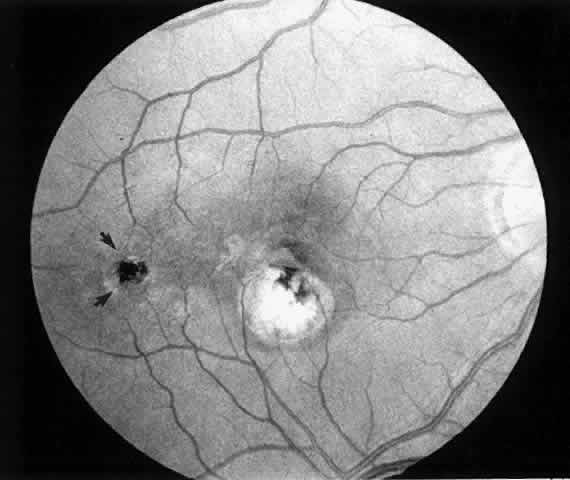

| Patients are examined 1 and 7 to 10 days after surgery to verify that intraocular pressure is acceptable, the retina remains attached, and no infection occurs. Three weeks after surgery, the view is usually adequate for assessment of the presence or absence of subfoveal RPE. Occasionally, residual subretinal blood will obscure the underlying tissues for a longer period of time. Within the first month, angiography is repeated to evaluate for recurrence of neovascularization. Not uncommonly, the site of the original choroidal ingrowth stalk demonstrates recurrent neovascularization. Often this site is not subfoveal and therefore slit lamp laser photocoagulation can be employed to ablate the recurrence. Given the fact that membranes recur in approximately one third of cases within 6 months, close follow-up is essential. |

MEMBRANES ANTERIOR TO RETINAL PIGMENT EPITHELIUM At the present time, we advise surgical extraction of a membrane only if the membrane appears to lie anterior to the RPE. In some cases, this is an easy determination to make preoperatively; in others, it is difficult. We study the macula with stereoscopic viewing at the slit lamp through a 60- or 78-diopter lens or with a contact lens. We also obtain color, stereo, 2× magnified views of the macula for subsequent review. The findings on clinical examination that suggest an anterior location may include the following:

Angiographic findings consistent with membranes anterior to the RPE include the following: